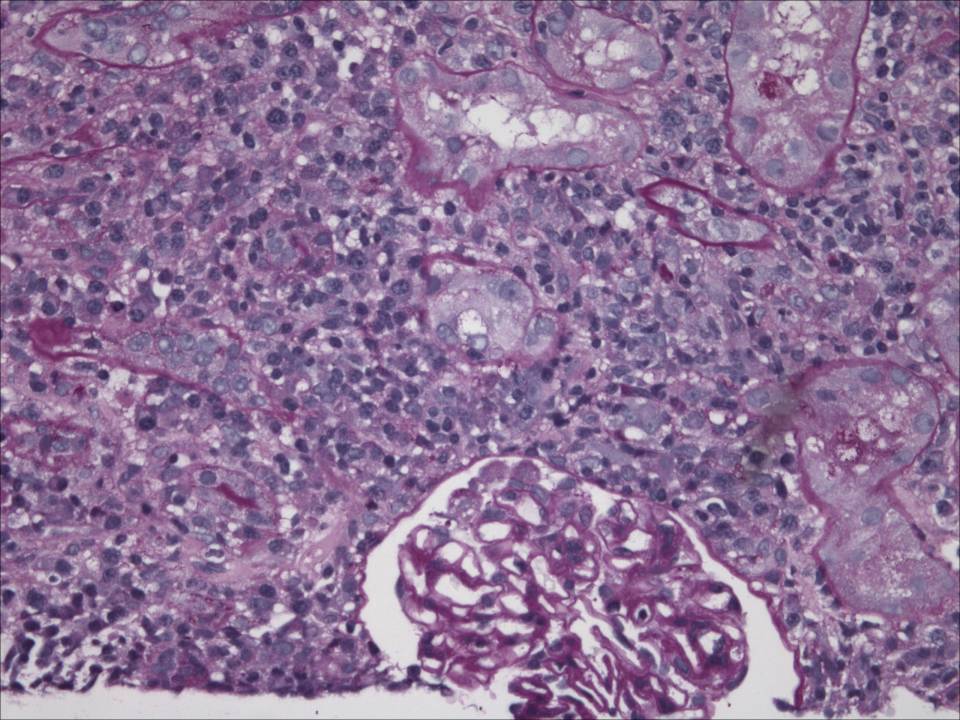

Higher power view of the cortex revealed relatively normal-appearing glomeruli with no inflammation and no crescents. There were some chronic changes with approximately 11% globally sclerosed glomeruli but this was not thought to be related to the current presentation.

There was a dense interstitial infiltrate with many plasma cells and occasional eosinophils. The small arterioles looked normal.